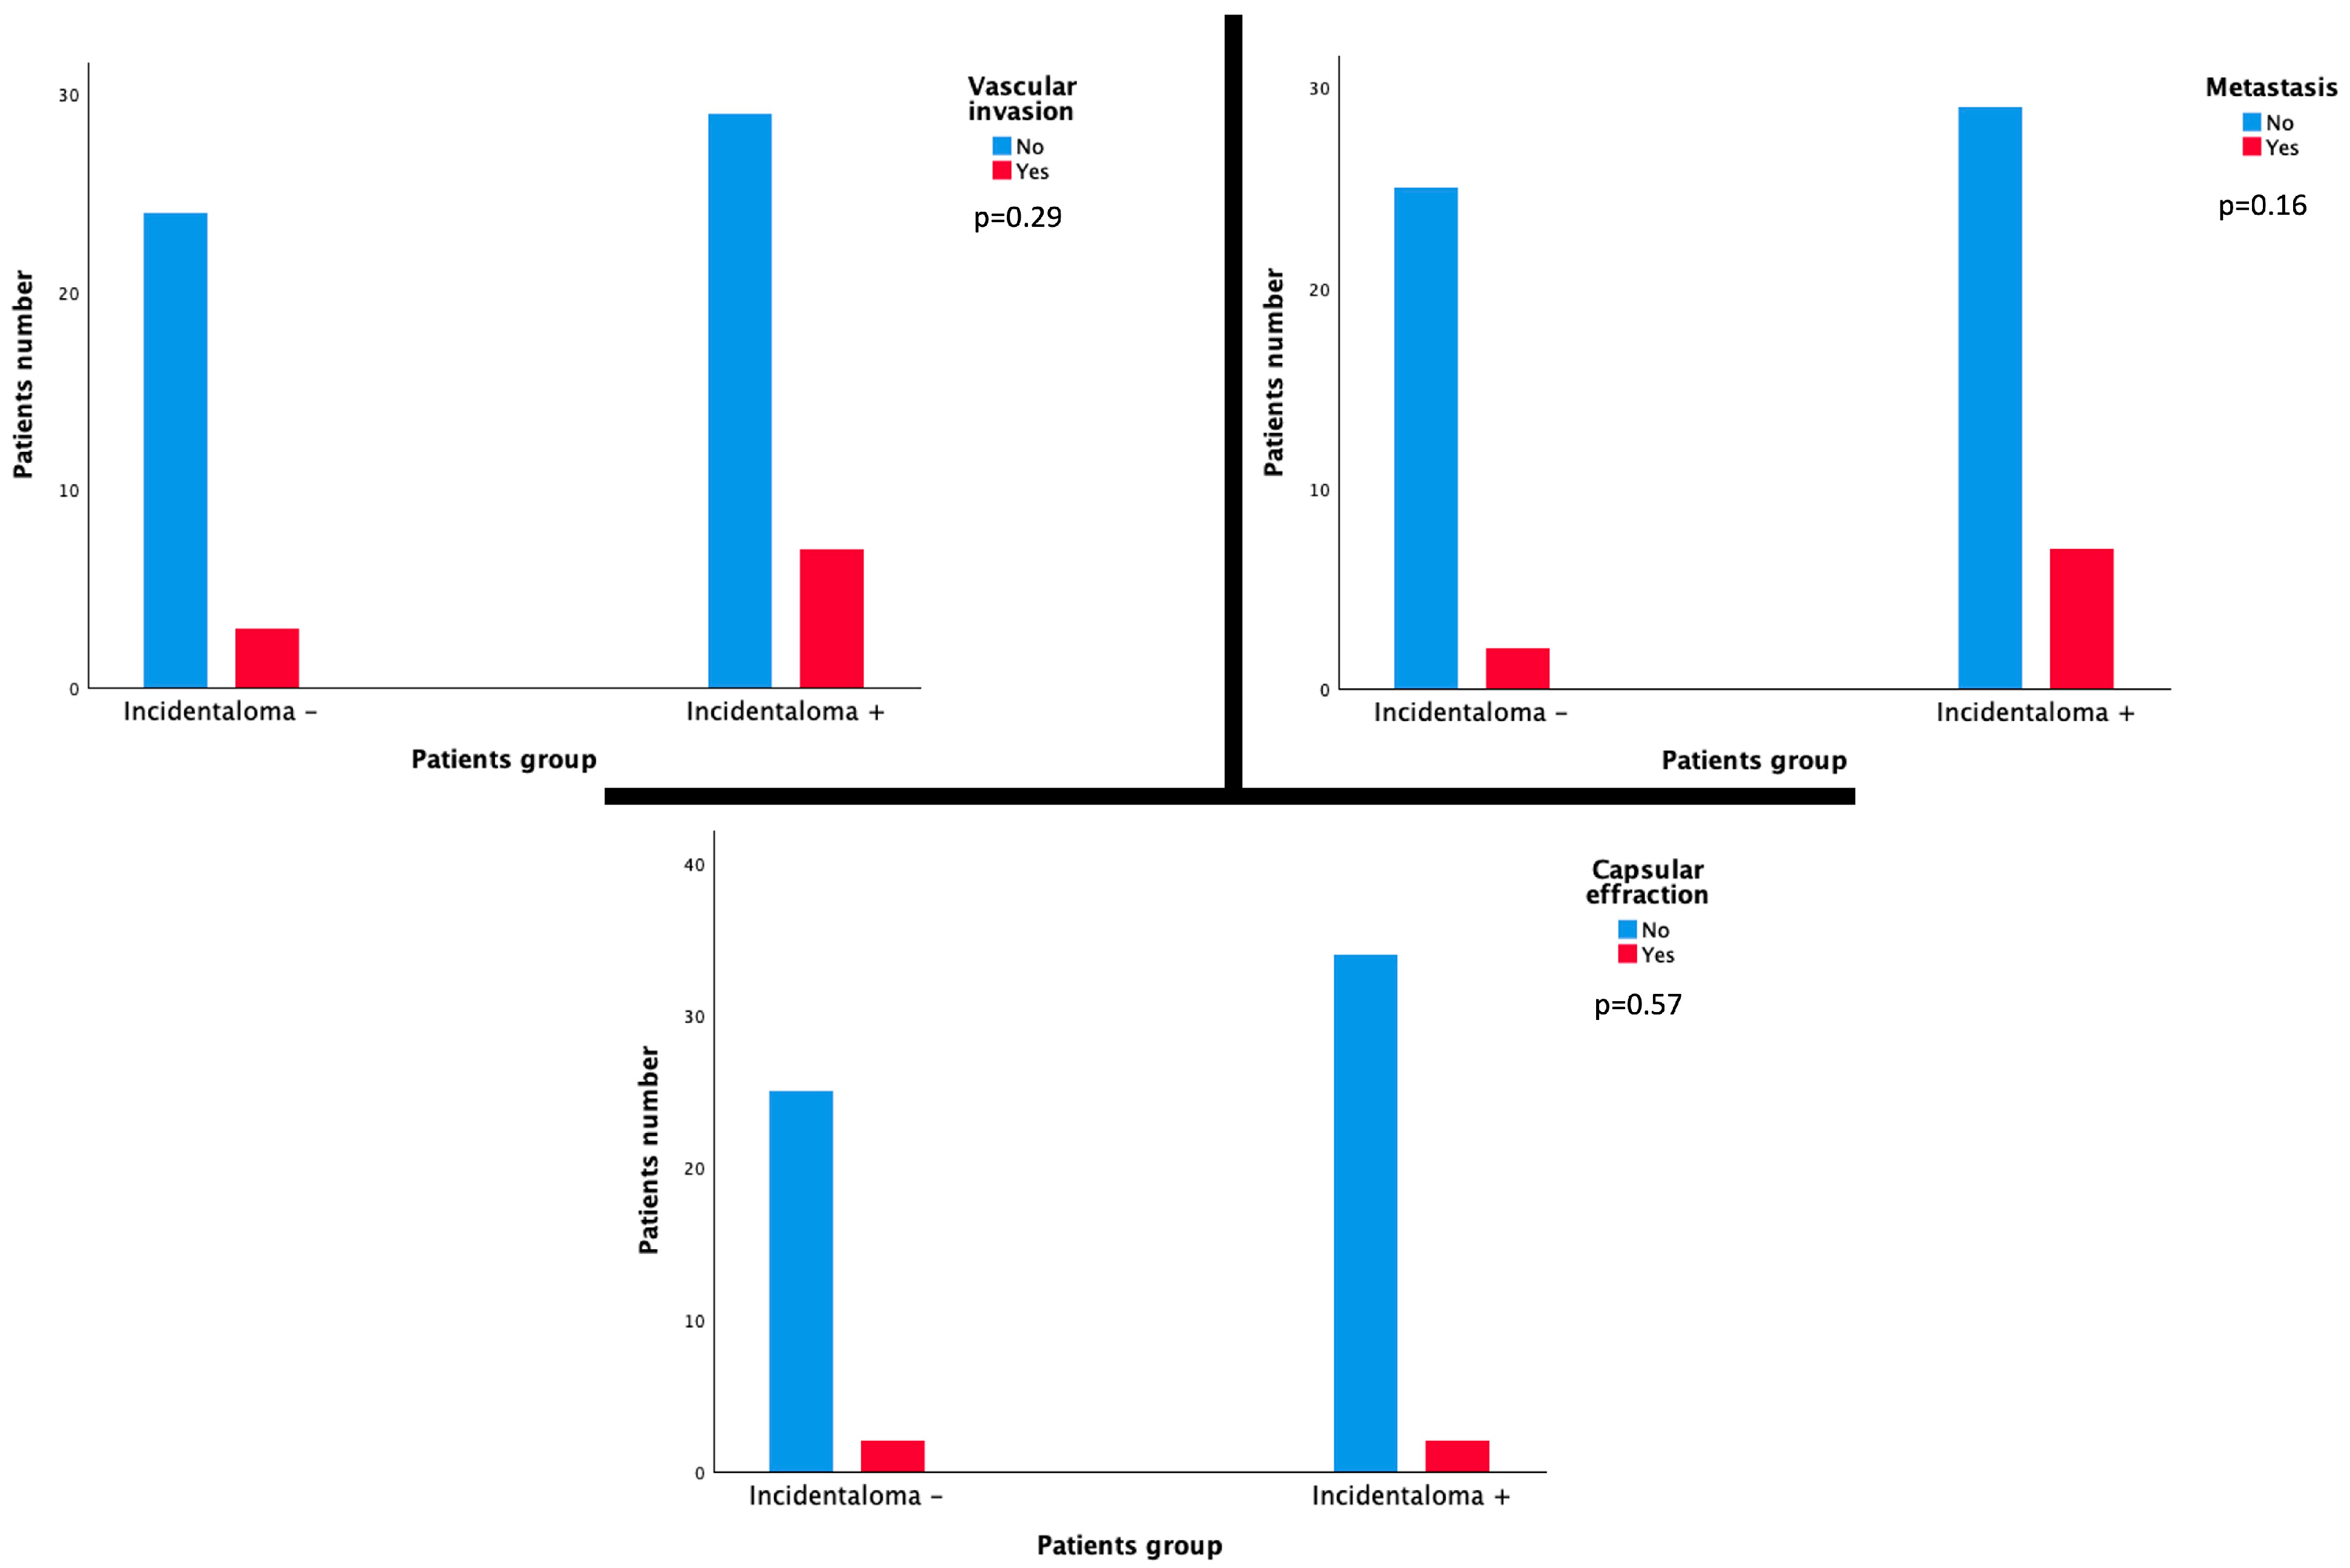

3.3. Correlation with Histopathological Features

3.4. Correlation with Patient Prognosis